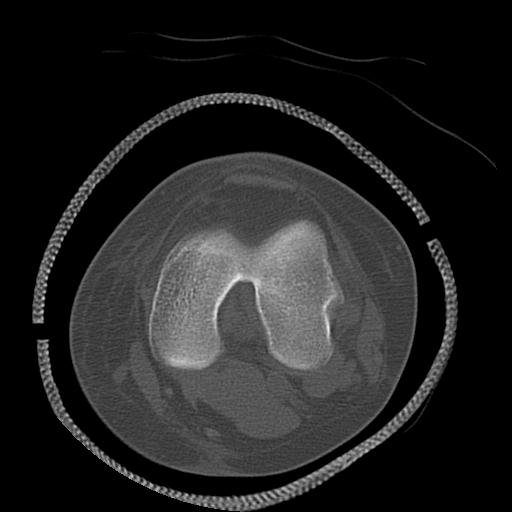

49554 3/13 膝 4R 3/16 4R 1/18 2R 78歳男性 膝蓋骨骨折